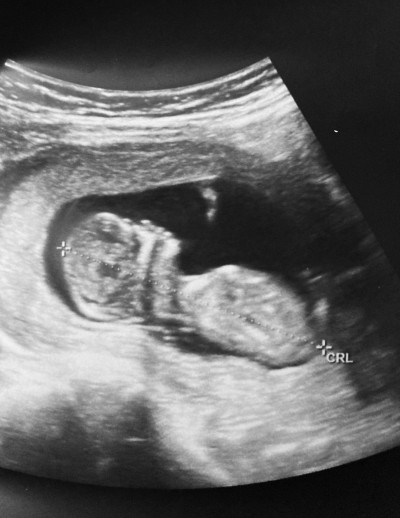

Sevgili anneler nub teoRisi bilenler yada cinsyst tahminlerine güvenenler yardımcı olabilr mi

Forografta 13 haftalık şuan 15 haftalık

Canım nub teorisi diye birşey var cinsiyeti %95 bilebiliyorlar

Canım erkke gibi nub a göre